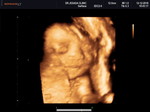

แพ้ท้องรึเปล่าค่ะ นอนพักเยอะๆจะดีขึ้นค้ะ

ลูกสาว